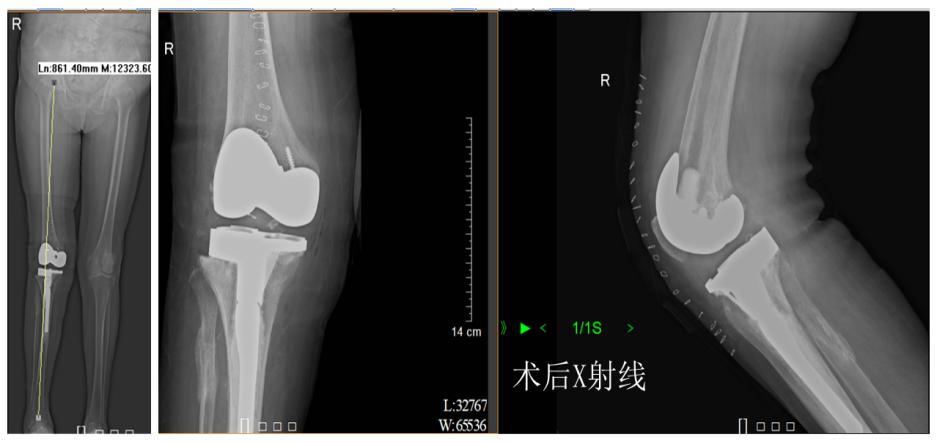

据了解,患者柯姨已经78岁了,20多年前,她的右膝出现反复疼痛的症状,并在10年前开始加重,导致活动困难甚至最后丧失了日常功能。但是,这么多年来柯姨一直讳疾忌医,不肯接受治疗。她的家属经过多方咨询、了解,最后选择来到茂名市人民医院关节四肢骨病外科住院手术治疗。术前X线片显示,柯姨的病症是右膝关节重度骨性关节炎,并重度外翻畸形,外翻角约30°。

术前术后X射线对比

据介绍,利用人工膝关节置换术治疗重度膝关节炎是公认的消除疼痛、矫正畸形、改善功能的有效方法,可以极大提高患者的生活质量。茂名市人民医院关节四肢骨病外科陈关林主任医疗团队经过充分术前讨论,为柯姨制定了合适的治疗方案,在腰硬联合麻下行右侧人工全膝关节置换术。整个手术用时近3小时,最后取得了非常满意的效果。术后,在尤英光护长带领的护理团队精心的护理及专业的康复锻炼下,可以很快就可以下地负重锻炼,并如期出院回家。柯姨及其家属为答谢该科医护人员,特意为他们送上锦旗。